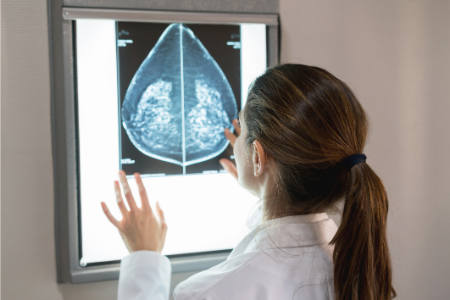

• بیماری پاژه سینه: یک نوع نادر سرطان سینه (1-4% موارد) که با قرمزی، پوستهپوسته شدن و ترشح همراه است. تشخیص با بیوپسی و درمان با جراحی.

چه زمانی به پزشک مراجعه کنید؟

اگر لکهها ظرف یک هفته برطرف نشدند، یا با علائم زیر همراه بودند، فوراً به پزشک مراجعه کنید:

• توده در سینه یا صاف شدن نوک سینه.

هر تغییر غیرعادی در سینه باید بررسی شود، زیرا سرطان سینه دومین علت مرگ ناشی از سرطان در زنان است.

2. آیا لکههای سفید روی نوک سینه میتوانند نشانه سرطان باشند؟

در موارد نادر، لکههای سفید ممکن است به دلیل بیماری پاژه سینه (نوعی سرطان نادر) یا فشار تومور روی مجاری شیری ایجاد شوند. اگر علائم بیش از یک هفته ادامه یافت یا غیرعادی بود، به پزشک مراجعه کنید.